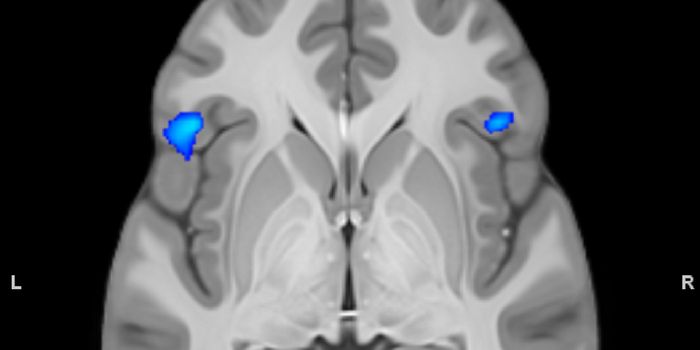

Read the latest articles about newly released neuroscience research and advances in experimental techniques. Topics include research news in neuroscience, neurology, psychology, brain science and cognitive sciences.